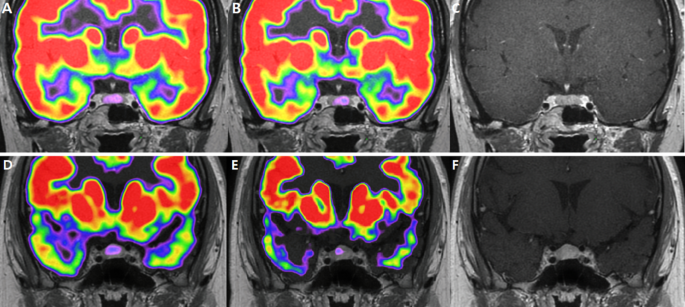

Corticotropin-dependent causes of Cushing’s syndrome are divided into those in which the corticotropin comes from the pituitary (eutopic causes) and those in which the corticotropin comes from elsewhere (ectopic causes). This differentiation is made with the measurement of corticotropin in inferior petrosal sinus plasma and the simultaneous measurement of corticotropin in peripheral (antecubital) plasma immediately after corticotropin-releasing hormone stimulation of pituitary corticotropin secretion. In samples obtained 4, 6, and 15 minutes after stimulation with corticotropin-releasing hormone, eutopic corticotropin secretion is associated with a ratio of the central-plasma corticotropin level to the peripheral-plasma corticotropin level of 3 or more. Ectopic corticotropin secretion is associated with a central-to-peripheral corticotropin ratio of less than 3. The positive predictive value of this test is 1 (Figure 4

FIGURE 4

Maximal Ratio of Corticotropin in Inferior Petrosal Sinus Plasma to Corticotropin in Peripheral Plasma in Patients with Cushing’s Syndrome, Ectopic Corticotropin Secretion, or Adrenal Disease.).28